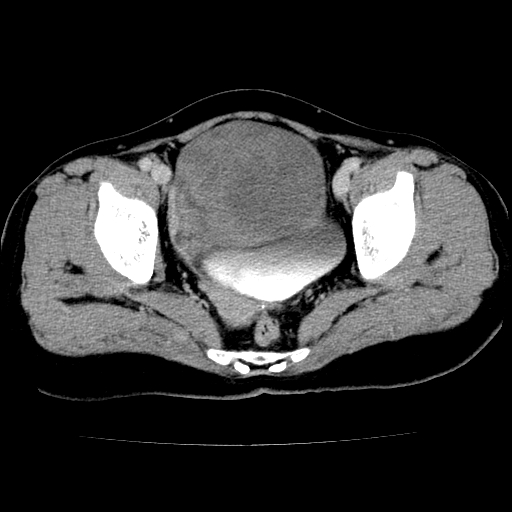

标题: CT24785:女,62岁,发现下腹部肿物半年。 [打印本页]

标题: CT24785:女,62岁,发现下腹部肿物半年。

女,62岁,发现下腹部肿物半年,下腹部不适。

考虑子宫平滑肌肉瘤可能性大。

实性成分太多,要是囊腺瘤也要考虑恶性。